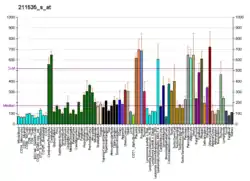

Somatic mutations and epigenetic changes in the expression of the FGFR1 gene occur in and are thought to contribute to various types of lung, breast, hematological, and other types of cancers.

Lung cancers

Amplification of the FGFR1 gene (four or more copies) is present in 9 to 22% of patients with non-small-cell lung carcinoma (NSCLC). FGFR1 amplification was highly correlated with a history of tobacco smoking and proved to be the single largest prognostic factor in a cohort of patients suffering this disease. About 1% of patients with other types of lung cancer show amplifications in FGFR1.[9][10][16][17]

Breast cancers

Amplification of FGFR1 also occurs in ~10% of estrogen receptor positive breast cancers, particularly of the luminal subtype B form of breast cancer. The presence of FGFR1 amplification has been correlated with resistance to hormone blocking therapy and found to be a poor prognostic factor in the disease.[9][10]

Hematological cancers

In certain rare hematological cancers, the fusion of FGFR1 with various other genes due to Chromosomal translocations or Interstitial deletions create genes that encode chimeric FGFR1 Fusion proteins. These proteins have continuously active FGFR1-derived tyrosine kinase and thereby continuously stimulated the cell growth and proliferation. These mutations occur in the early stages of myeloid and/or lymphoid cell lines and are the cause of or contribute to the development and progression of certain types of hematological malignancies that have increased numbers of circulating blood eosinophils, increased numbers of bone marrow eosinophils, and/or the infiltration of eosinophils into tissues. These neoplasms were initially regarded as eosinophilias, hypereosinophilias, Myeloid leukemias, myeloproliferative neoplasms, myeloid sarcomas, lymphoid leukemias, or non-Hodgkin lymphomas. Based on their association with eosinophils, unique genetic mutations, and known or potential sensitivity to tyrosine kinase inhibitor therapy, they are now being classified together as clonal eosinophilias.[6] These mutations are described by connecting the chromosome site for the FGFR1 gene, 8p11 (i.e. human chromosome 8's short arm [i.e. p] at position 11) with another gene such as the MYO18A whose site is 17q11 (i.e human chromosome 17's long arm [i.e. q] at position 11) to yield the fusion gene annotated as t(8;17)(p11;q11). These FGFR1 mutations along with the chromosomal location of FGFR1A's partner gene and the annotation of the fused gene are given in the following table.[18][19][20]

Acquired abnormalities if the FGFR1 gene are found in: ~14% of urinary bladder Transitional cell carcinomas (almost all are amplifications); ~10% of squamous cell Head and neck cancers (~80% amplifications, 20% other mutations); ~7% of endometrial cancers (half amplifications, half other types of mutations); ~6% of prostate cancers (half amplifications, half other mutations); ~5% of ovarian Papillary serous cystadenocarcinoma (almost all amplifications); ~5% of colorectal cancers (~60 amplifications, 40% other mutations); ~4% of sarcomas (mostly amplifications); <3% of Glioblastomas (Fusion of FGFR1 and TACC1 (8p11) gene); <3% of Salivary gland cancer (all amplifications); and <2% in certain other cancers.[11][26][27]